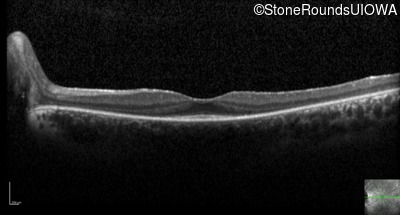

Optical Coherence Tomography - Left - 20/20 -2

Exemplar / OCT Stack

OCT Stack